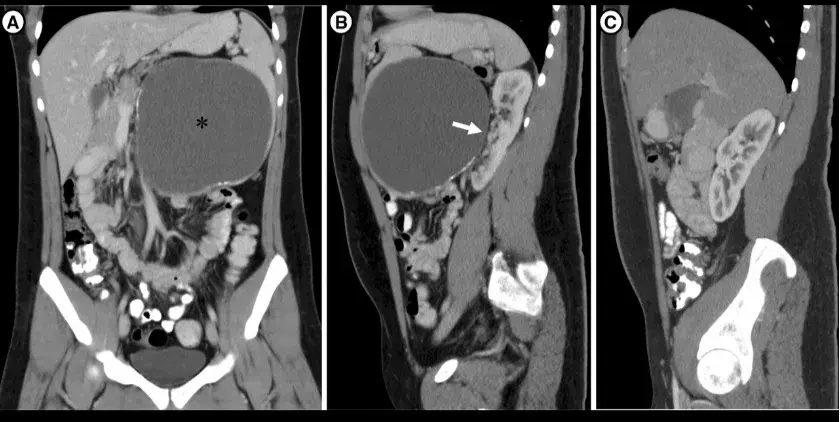

Por que é tão importante avaliar sódio em urina de 24h na DRC?

Por que é tão importante avaliar sódio em urina de 24h na DRC?

Avaliação do sódio em urina de 24 horas pode fornecer inúmeras informações ao nefrologista. Confere esse estudo.